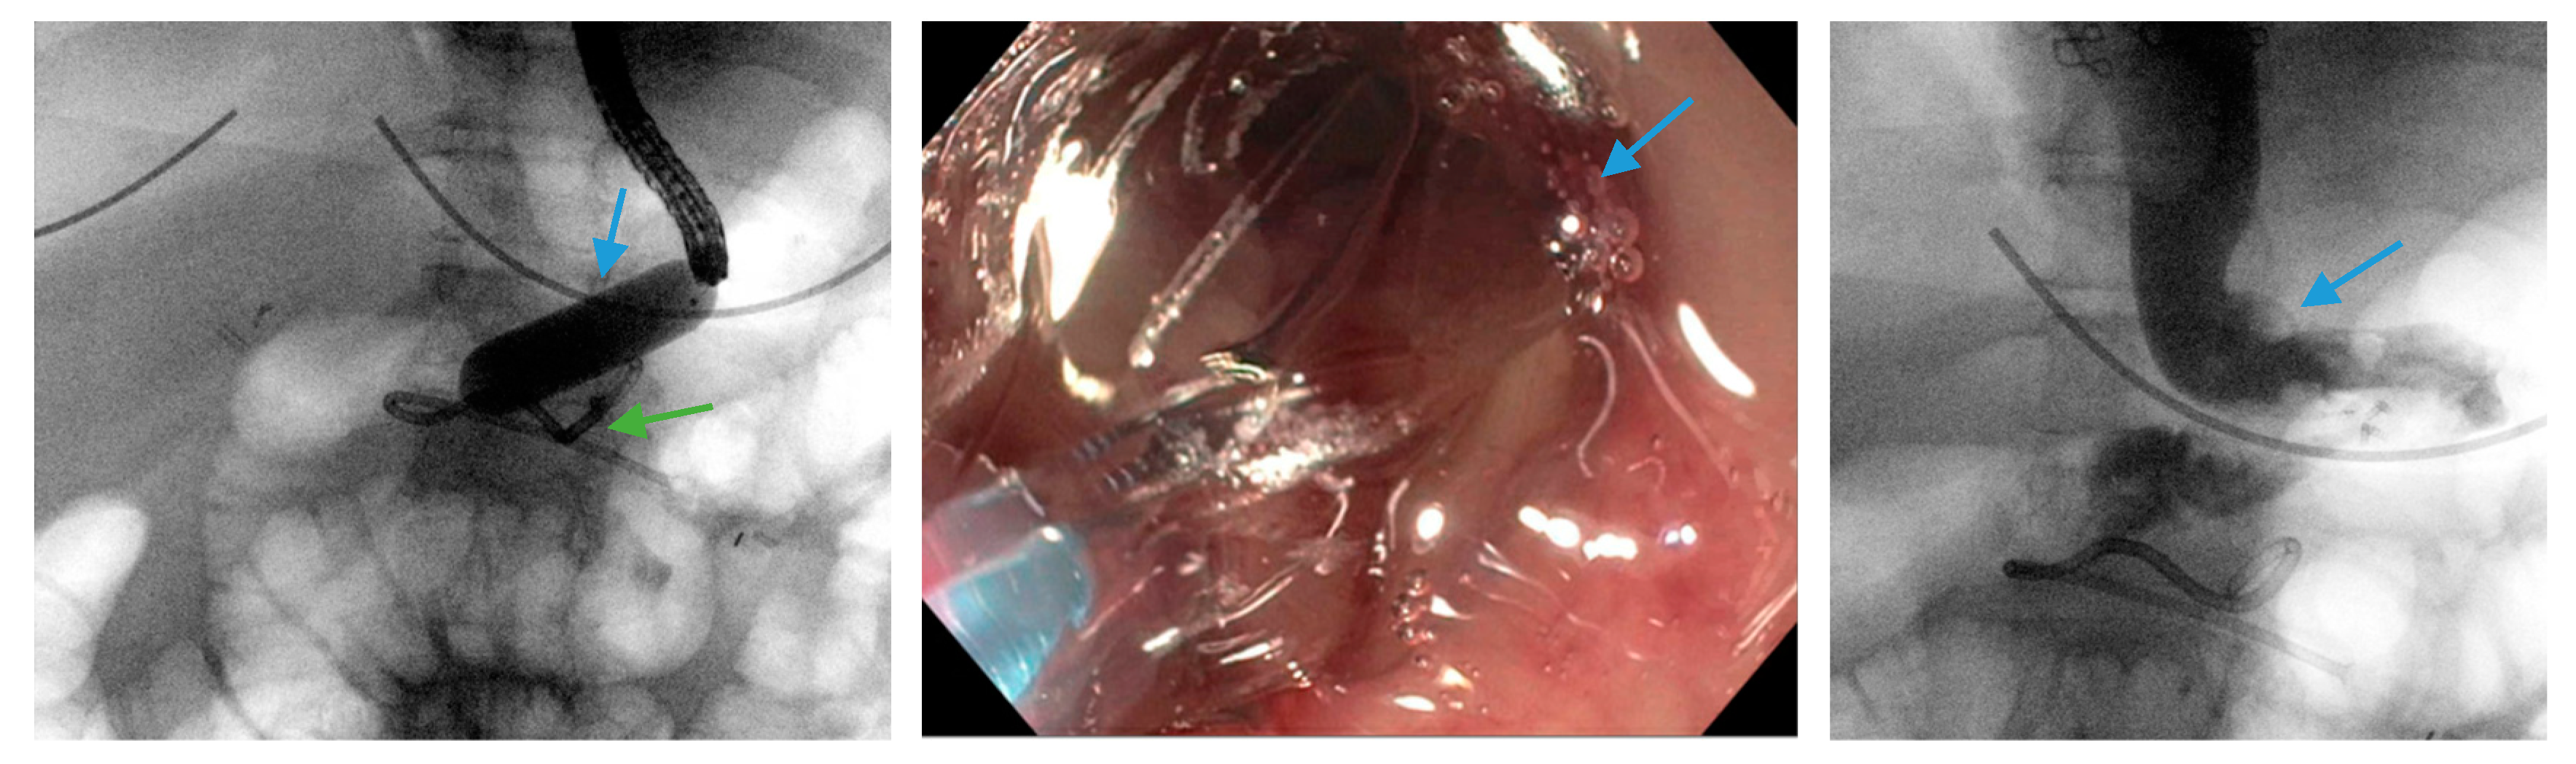

Figure 1.

Upper gastrointestinal series reveals a 23 mm × 15 cm fully-covered esophageal self-expanding metal stent from the distal esophagus to the mid portion of the sleeve anchored by two through-the-scope clips (blue arrows) and one over-the-scope clip (green arrow) placed on the proximal edge of the stent.

Scheme 6.

Upper endoscopy reveals the proximal (blue arrows, left) and distal edge (blue arrows, middle) of a fully-covered esophageal self-expanding metal stent anchored by two through-the-scope clips (blue arrows, right) and an over-the-scope clip (green arrows, right). Note copious saliva collected around the non-peristaltic prosthesis.